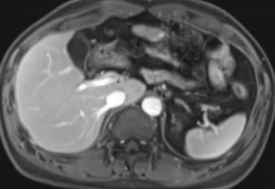

(1)上腹部增强核磁:提示肝左叶明显缩小,左肝静脉闭塞,考虑闭塞性静脉炎导致肝左叶废用性萎缩,肝右叶代偿性饱满。